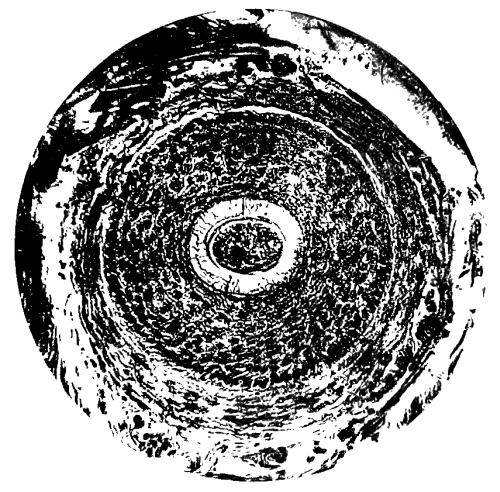

3. Photo-micrograph of transverse section of Normal Hair Follicle 27